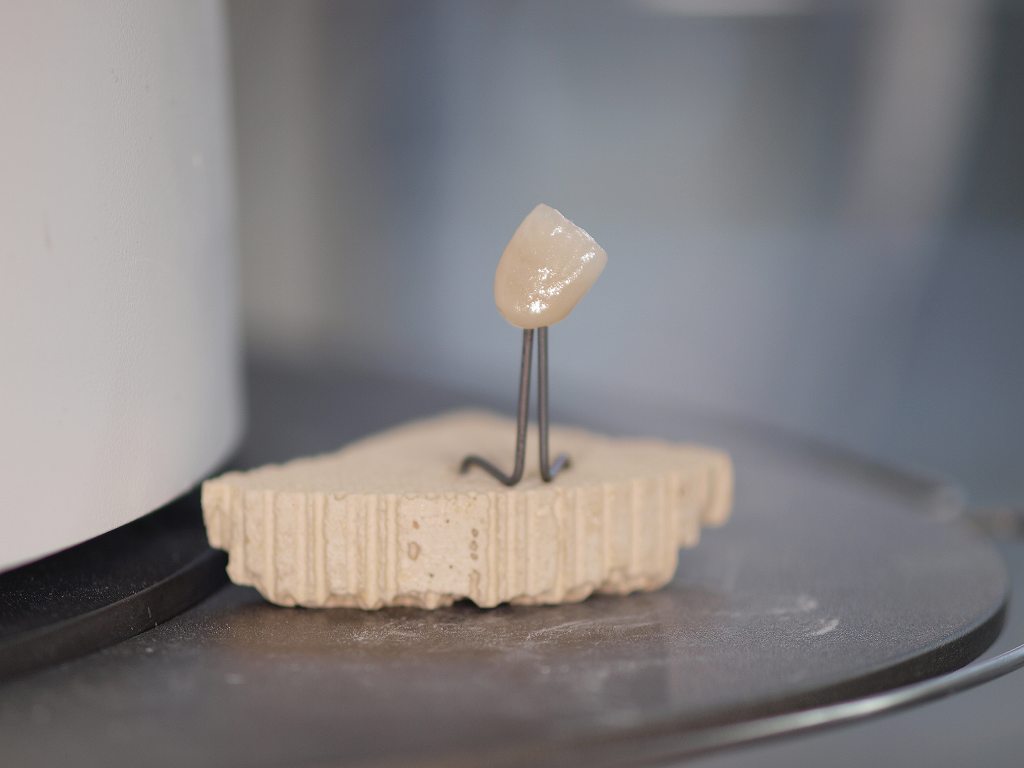

前歯部のセラミッククラウンにはジルコニアクラウンとオールセラミッククラウンの2通りが存在します。 オールセラミッククラウンはe-maxといわれるイボクラ社のガラス系二ケイサンリチウムをフレームとして使用していき、レイヤリングの形態をとります。|お知らせ |広島市安佐南区の歯科医院

前歯部のセラミッククラウンにはジルコニアクラウンとオールセラミッククラウンの2通りが存在します。 オールセラミッククラウンはe-maxといわれるイボクラ社のガラス系二ケイサンリチウムをフレームとして使用していき、レイヤリングの形態をとります。

前歯部のセラミッククラウンにはジルコニアクラウンとオールセラミッククラウンの2通りが存在します。 オールセラミッククラウンはe-maxといわれるイボクラ社のガラス系二ケイサンリチウムをフレームとして使用していき、レイヤリングの形態をとります。